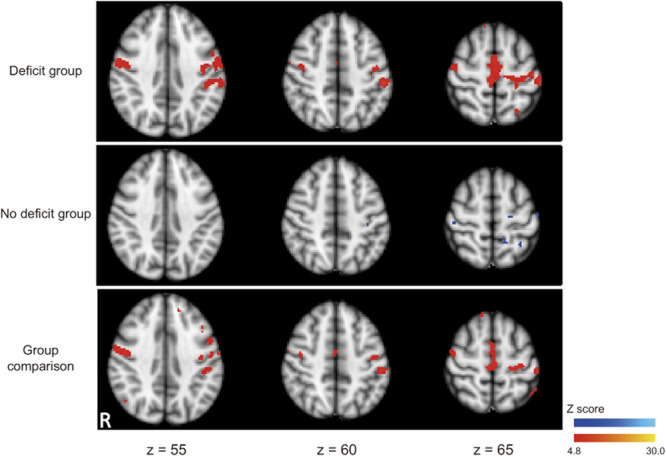

Methods: Twelve patients with brain tumors underwent preoperative and postoperative sessions consisting of motor performance evaluation and 3T-magnetic resonance imaging data acquisition. Based on additional postsurgical motor deficits, 6 patients were classified into "deficit group," and 6 others were into "no deficit group." Using resting-state functional magnetic resonance imaging (fMRI), the integrity of functional connectivity was evaluated by placing a seed in the ipsilesional primary motor area (M1). With motor task fMRI, hand and foot representations were identified in the M1 and lateral and medial PMs. Probabilistic tractography assessed anatomic connectivity in the cortico-cortical and corticofugal networks.

Results: Functional connectivity among M1 and lateral and medial PMs during resting-state fMRI was reduced postoperatively in the deficit group (P < .05, corrected) and preserved in the no deficit group. The deficit was unlikely to be attributable to surgical resection of specific anatomic connectivity. The amplitude of motor-evoked potential was maintained in available cases. These intraoperative observations agree with imaging findings suggesting preserved anatomic connectivity of the estimated corticofugal pathway.